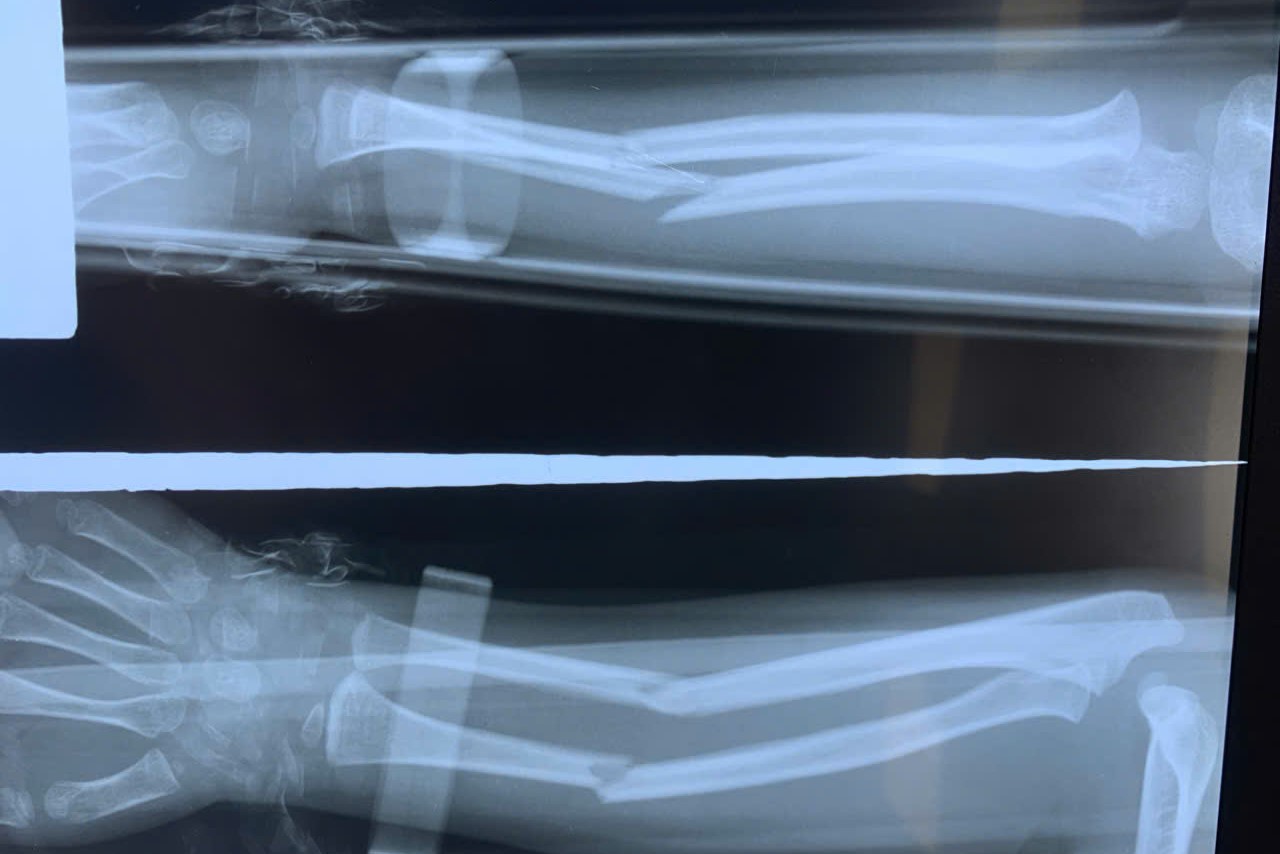

Máy C-arm (X-quang tại chỗ) hoạt động như một "đôi mắt xuyên thấu", cung cấp hình ảnh trực tiếp, chất lượng cao về xương gãy, cho phép phẫu thuật viên nắn chỉnh và cố định xương bằng đinh hoặc dụng cụ chuyên biệt chỉ qua các vết trích nhỏ (dưới 1cm). Kỹ thuật hiện đại này giúp nhân viên y tế thao tác chính xác mà không cần phá hủy mô mềm và bao khớp bao quanh ổ gãy.

Các vị trí gãy xương chi thể đã ứng dụng được phương pháp này như gãy xương cánh tay, cẳng tay, xương đùi, xương cẳng chân, ngón chân, ngón tay…